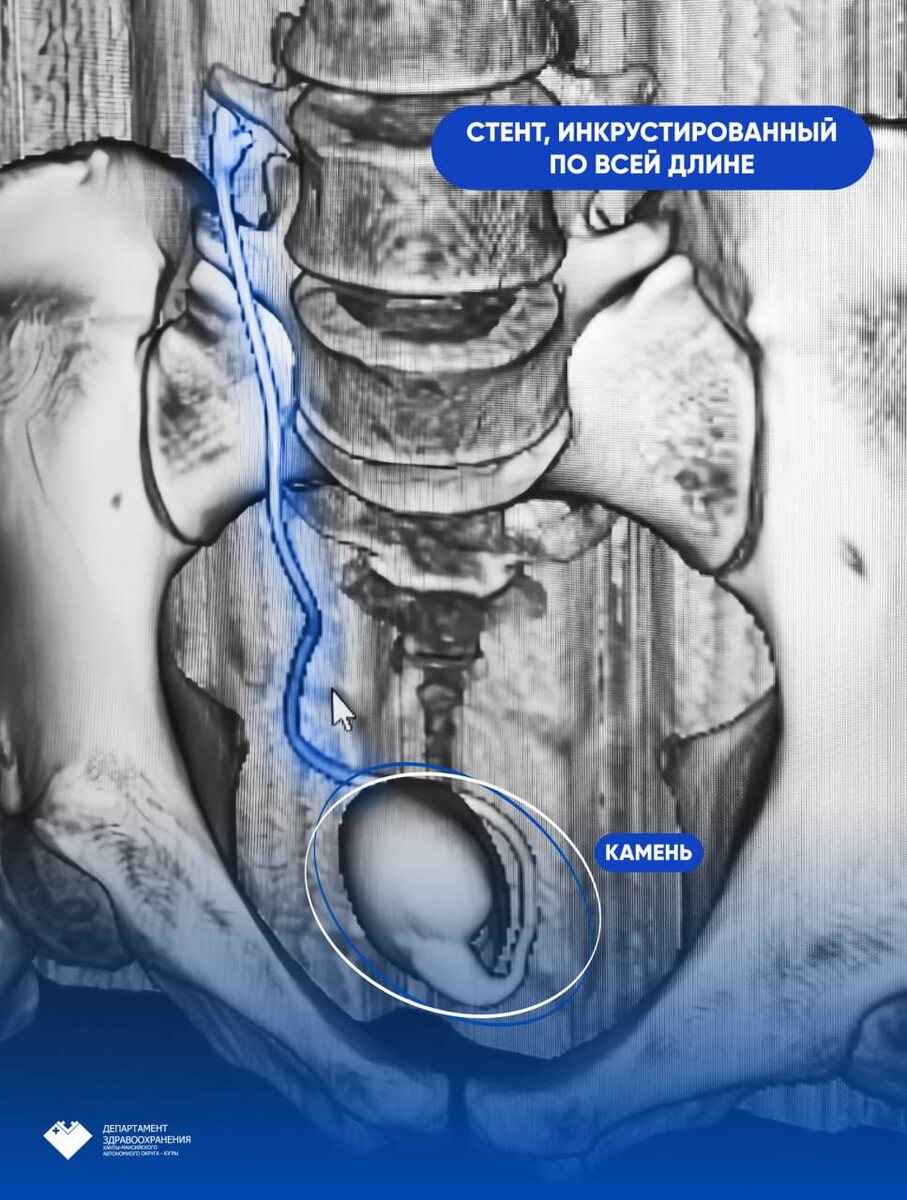

Мужчина из другого региона, находясь в Нижневартовске, пожаловался на частое болезненное мочеиспускание с примесью крови. В ходе обследования выяснилось: семь лет назад мужчине установили стент в правую почку. Назначенный срок эксплуатации такого стента — до одного года.

Стент в почке у пациента уже «оброс» камнями, из-за этого в мочевом пузыре появился еще один камень.